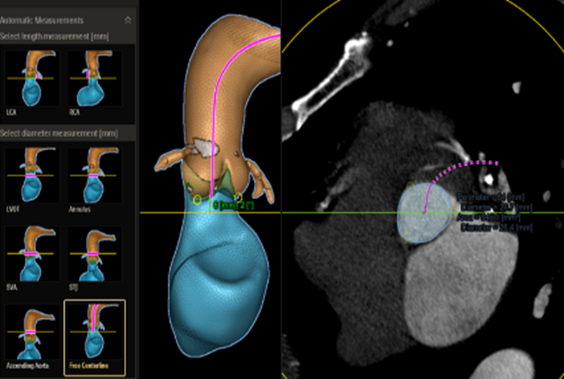

HeartNavigator

Azurion(아주리온)은 최신 인터벤션 소프트웨어가 탑재되어 있어 심혈관중재시술 시 더욱 용이하게 환자를 시술할 수 있도록 해준다. 최근 도입된 다이내믹 코로너리 로드맵(Dynamic Coronary Roadmap)과 스텐트부스트 라이브 (StentBoost Live)는 복잡하고 어려운 심장 혈관 및 심장 구조 질환의 치료에 성공적인 시술을 할 수 있도록 도와준다. 두 기술 모두 까다로운 심혈관중재시술 시 실시간 레퍼런스로 활용할 수 있어, 시술 시간의 단축, 방사선 피폭 및 조영제 사용량을 최소화할 수 있다.